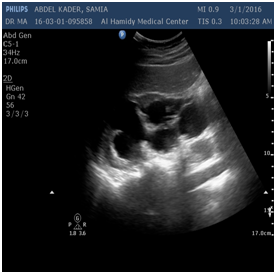

The disease if not treated may progress to the ureters and cause hydronephrosis (Figure 6) or may metastasize to another areas. During my practice I noted that 20 % (about 40 cases) of tumor recurrence occurred, mostly because the patient's did not quit smoking.

Figure 6 Moderate to severe hydronephrosis due to outlet obstruction.